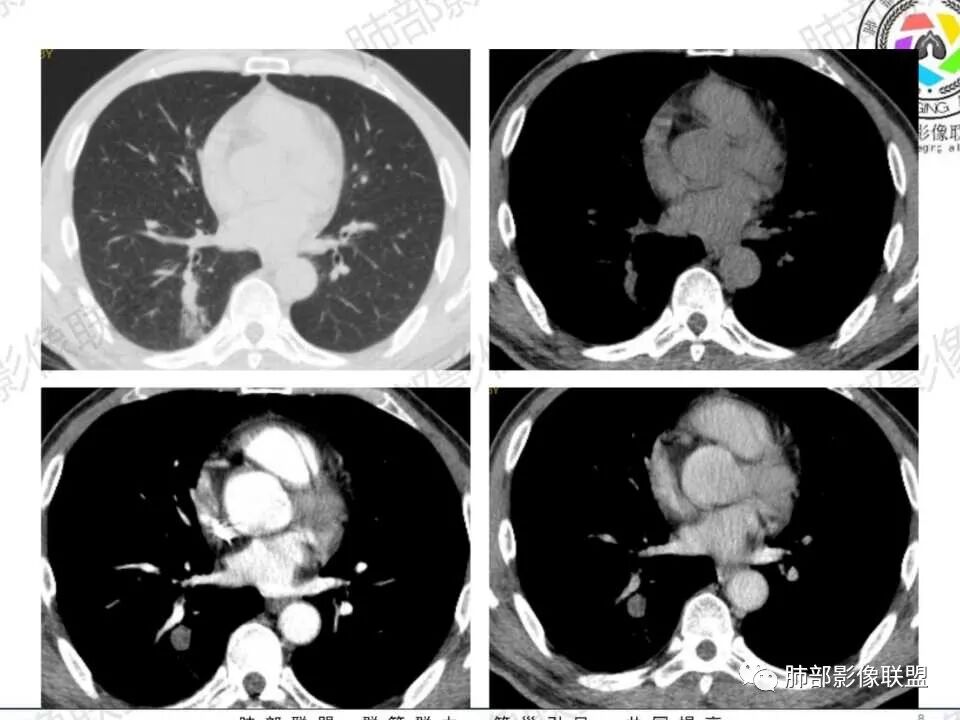

中年男性,糖尿病史,无症状。右肺下叶类圆形结节,边缘光滑,支气管近端阻塞,远端淡片影,树芽还是阻塞性炎症?感觉像树芽,沿支气管分布,无明显强化,治疗一周后复查CT,支气管通而不畅,近端小空洞,远端淡片影加重。考虑肺结核可能性大,鉴别肺癌并阻塞性肺炎。

中年男性,糖尿病史,无症状。右肺下叶类圆形结节,边缘光滑,远端树芽征,沿支气管分布,无明显强化,治疗一周后复查CT,支气管通而不畅,近端小空洞,远端树芽征进展为磨玻璃影。考虑肺结核可能性大。

中年男性患者,有糖尿病基础。右下肺结节较1年前增大,CT表现:右肺下叶后段类圆形结节,边界清楚,边缘部分膀隆、部分平直,内部大部分密度均匀,其中见小条状低密度影(粘液栓?),近端支气管堵塞(抗感染治疗后见大部分通畅,近端支气管进入截断入口圆钝、远端支气管稍扩张),综合考虑结核可能性大,治疗后病灶呈支气管挂果,注意鉴别错构瘤。

复查时支气管似乎通了

腔内似乎有物质堵塞

但是结节内出现含气影

远端楔形,符合阻塞的特点

增强还是有强化,整体边缘平直

觉得远端是小树芽